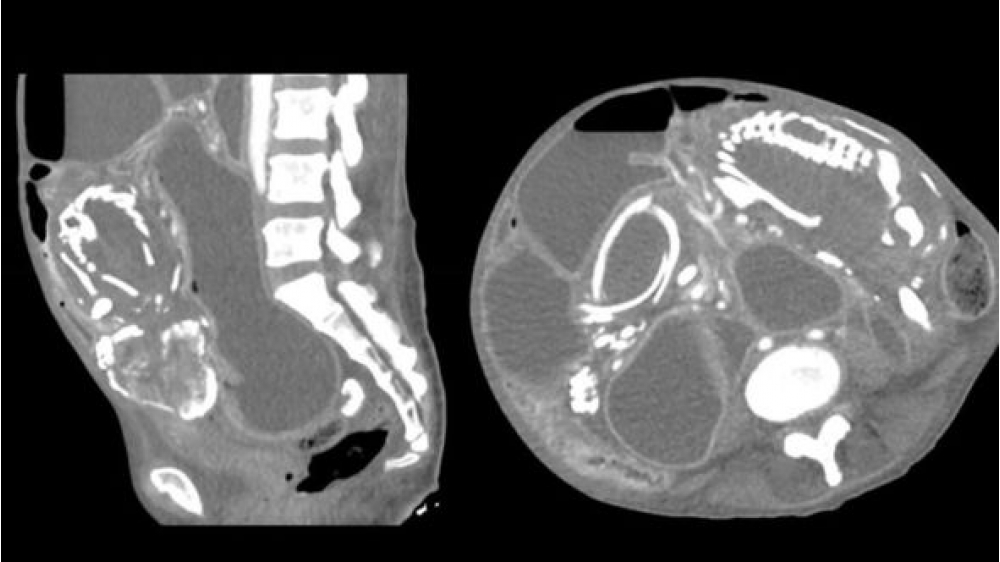

Ancaq doqquz il sonra Nyu-Yorka köçən afrikalı yenə də öz sözünü pozub və mədəsində həzm problemləri şikayəti ilə xəstəxanaya gəlib. Müayinə zamanı qadının orqanizmində həzm sisteminə təzyiq göstərən və həyati vacib qidaların orqanizmə daxil olmasına mane olan artıq daşlaşmış dölün olması müəyyən edilib.

Həkimlər xəstəyə əməliyyat olunmasını və ölən uşağı çıxartmağı təklif ediblər, lakin miqrant hər şeyin günahının Tanzaniyada ona söylənən lənətlərin olduğunu deyərək bundan imtina edib. Qadın həkimlərə öz vəziyyətini nəzarətdə saxlamağa və halı pisləşərsə, tibb işçilərinə müraciət edəcəyini vəd edib. Lakin həkimlərlə qadının növbəti “görüşü” artıq meyitxanada baş tutub. Yarılma zamanı normal qidalana bilməyən orqanizmin tükənməsi ölümün səbəbi kimi qeydə alınıb.